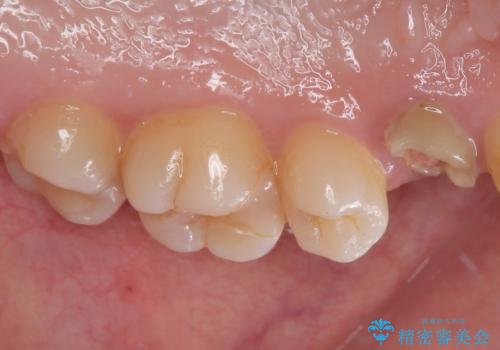

左上小臼歯を抜歯し、矯正治療でスペースを閉じる方法と左上小臼歯を抜歯し、抜歯即時インプラントを行う方法、保存療法を行う方法の治療期間、費用、メリット・デメリットについて説明したうえで治療期間をできるだけ短くしたいという希望があったため抜歯即時インプラント治療を選択されました。